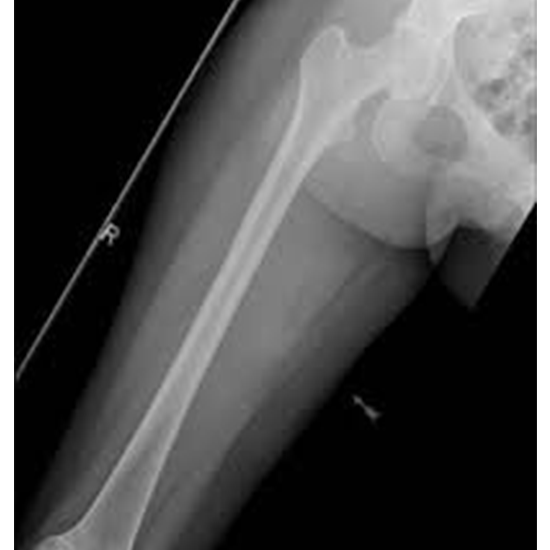

The femur X-ray shows the soft tissues and the femur, the bone in the upper leg.

A femur X-ray can diagnose upper leg pain, limping, tenderness, edema, or deformity. It can show a broken bone and if it's aligned and healed appropriately after it's been set.

X-rays help surgeons plan and monitor the surgery. It can also help find cysts, tumors, or other diseases in the bone, such as bone infections in their later stages.